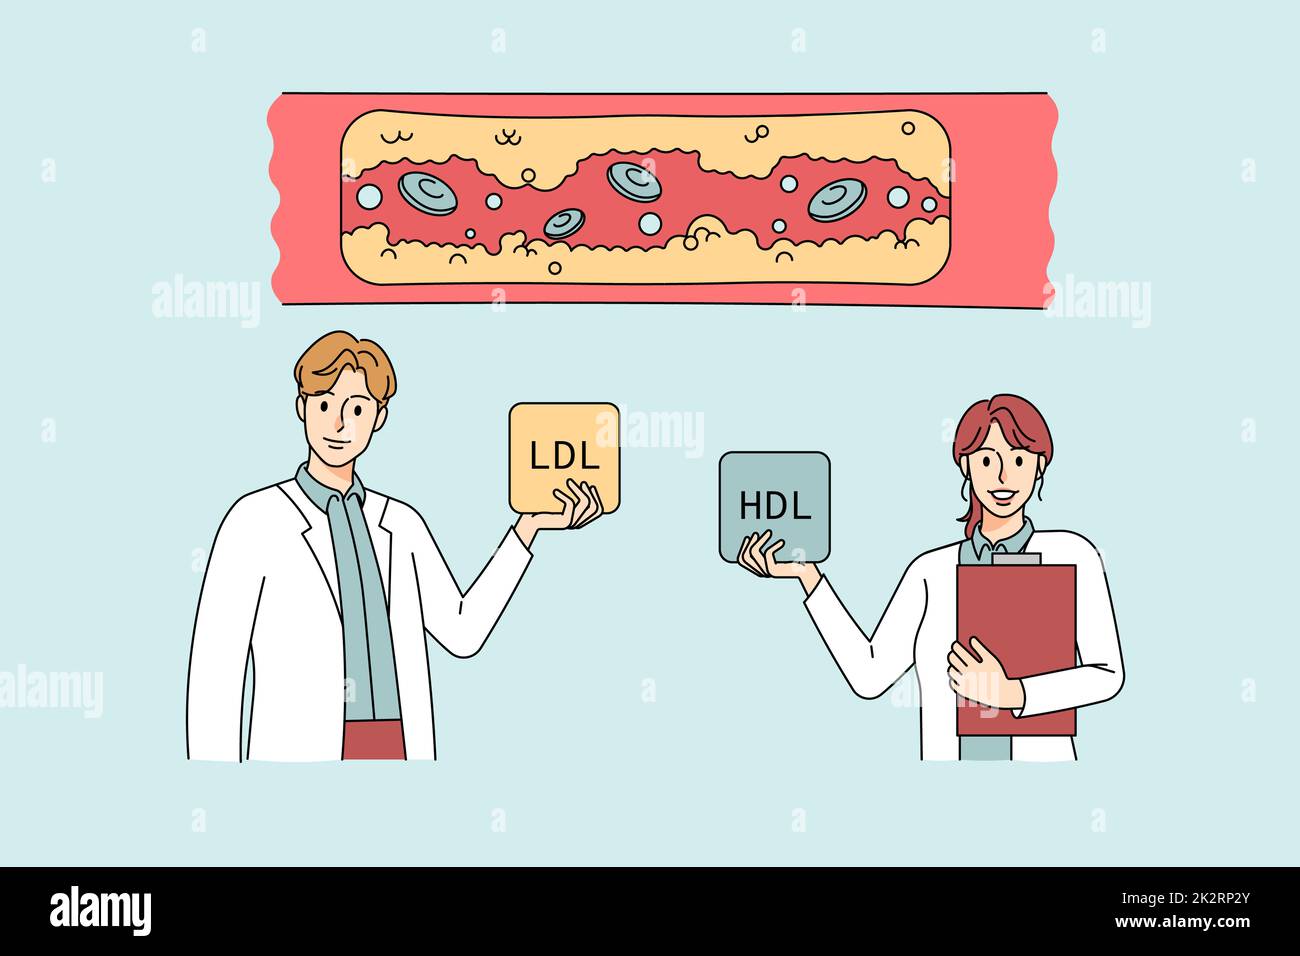

Doctors show levels of cholesterol in human vessels Stock Photohttps://www.alamy.com/image-license-details/?v=1https://www.alamy.com/doctors-show-levels-of-cholesterol-in-human-vessels-image483641843.html

Doctors show levels of cholesterol in human vessels Stock Photohttps://www.alamy.com/image-license-details/?v=1https://www.alamy.com/doctors-show-levels-of-cholesterol-in-human-vessels-image483641843.htmlRF2K2RP2Y–Doctors show levels of cholesterol in human vessels